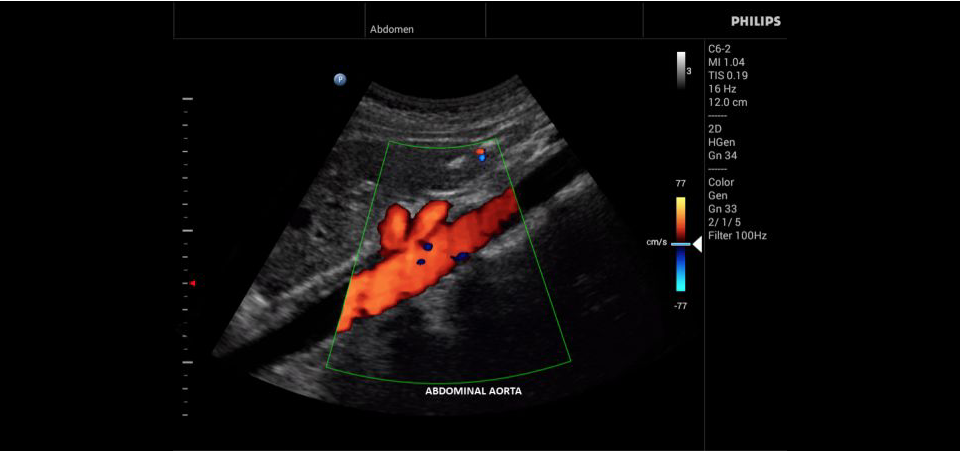

• Конвексный УЗИ датчик Philips С6-2

• Исследования сосудов;

• Цветное допплеровское картирование

• Общие абдоминальные исследования;